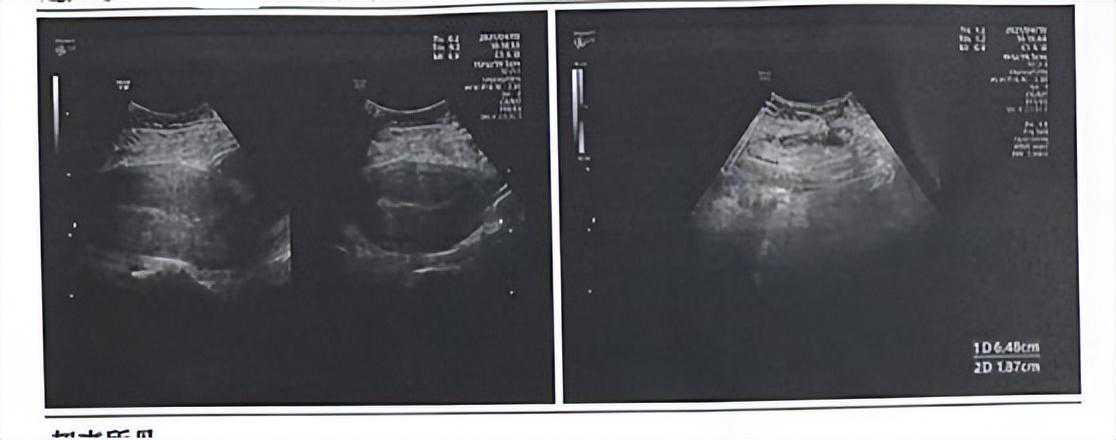

患者稍恢复后,予以复查妇科超声,提示子宫增大,腔内异常回声,子宫左前方异常回声。这种情况可能是患者腔内有尚未机化吸收的血块,且患者目前生命体征平稳,暂时不予处理,出院后半月回院复查即可。